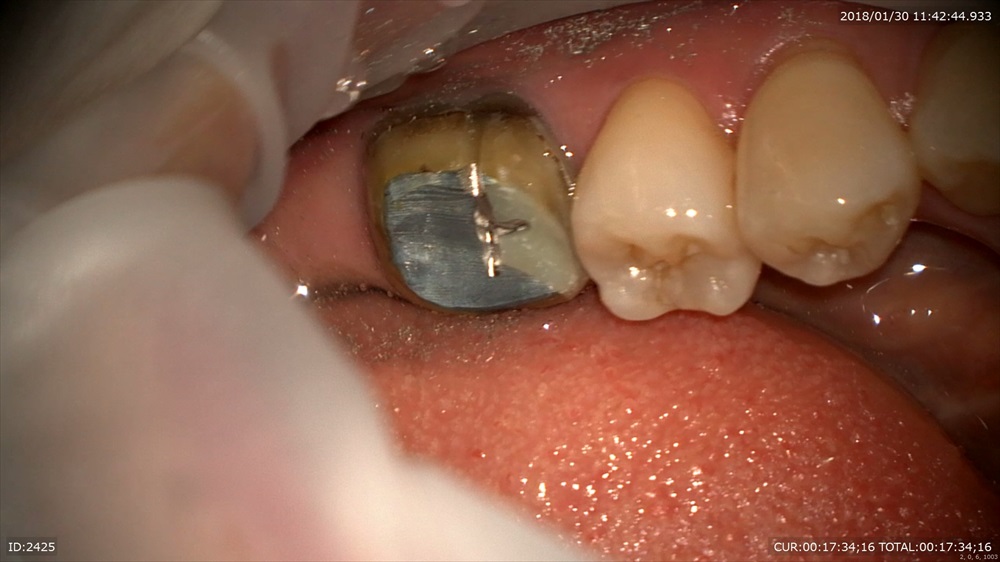

下の方のようにかぶせ物があっていないと根管内に細菌感染が起こり再発する可能性が高くなるわけです。

今日は外して感染源を除去。マイクロスコープで行うから血が一切でません。